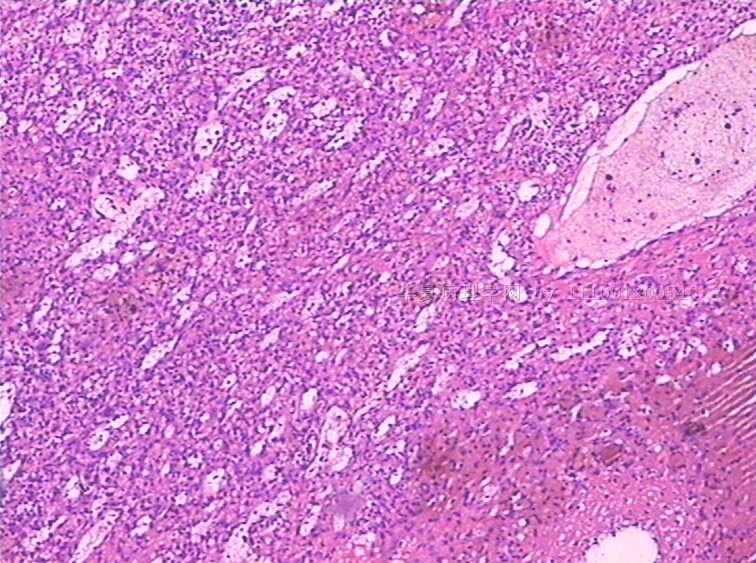

女

49

反复发热,全血细胞下降1月余.CT示肝、脾肿大。骨髓检查:增生活跃,红系增高。

手术所见:脾巨大,内有梗死。肝表面光滑、肿胀。肝门淋巴结肿大,无腹水。

巨检:脾切除一个,20×15×8cm.切面灰红,有多个灰白区,最大8×6×3cm,呈楔性,小者绿豆大小

见到一些异型细胞,细胞质几乎看不到。考虑为淋巴造血系统肿瘤,脾脏原发淋巴瘤可能。